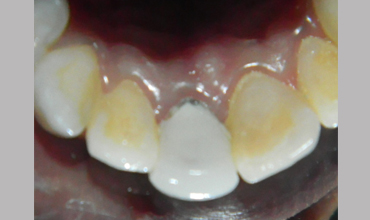

Post Core

Management Of Fractured Tooth With Cast Post & Core